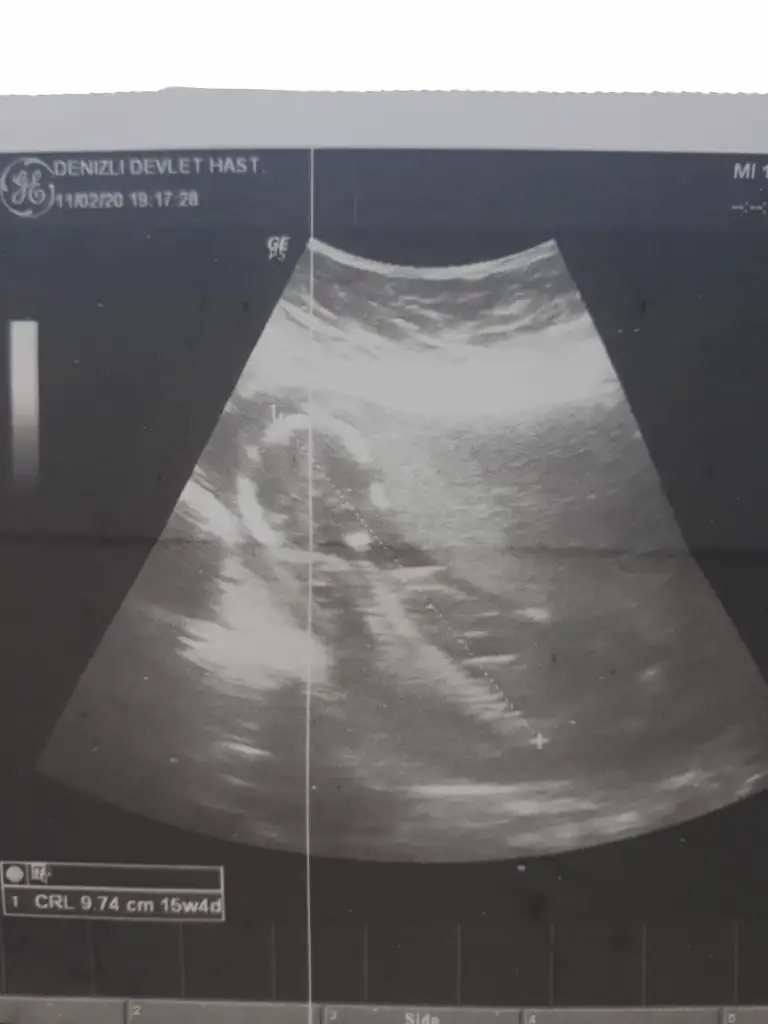

dr soylemeden siz gorun genital nub teorisi ( bebegin cinsiyeti)